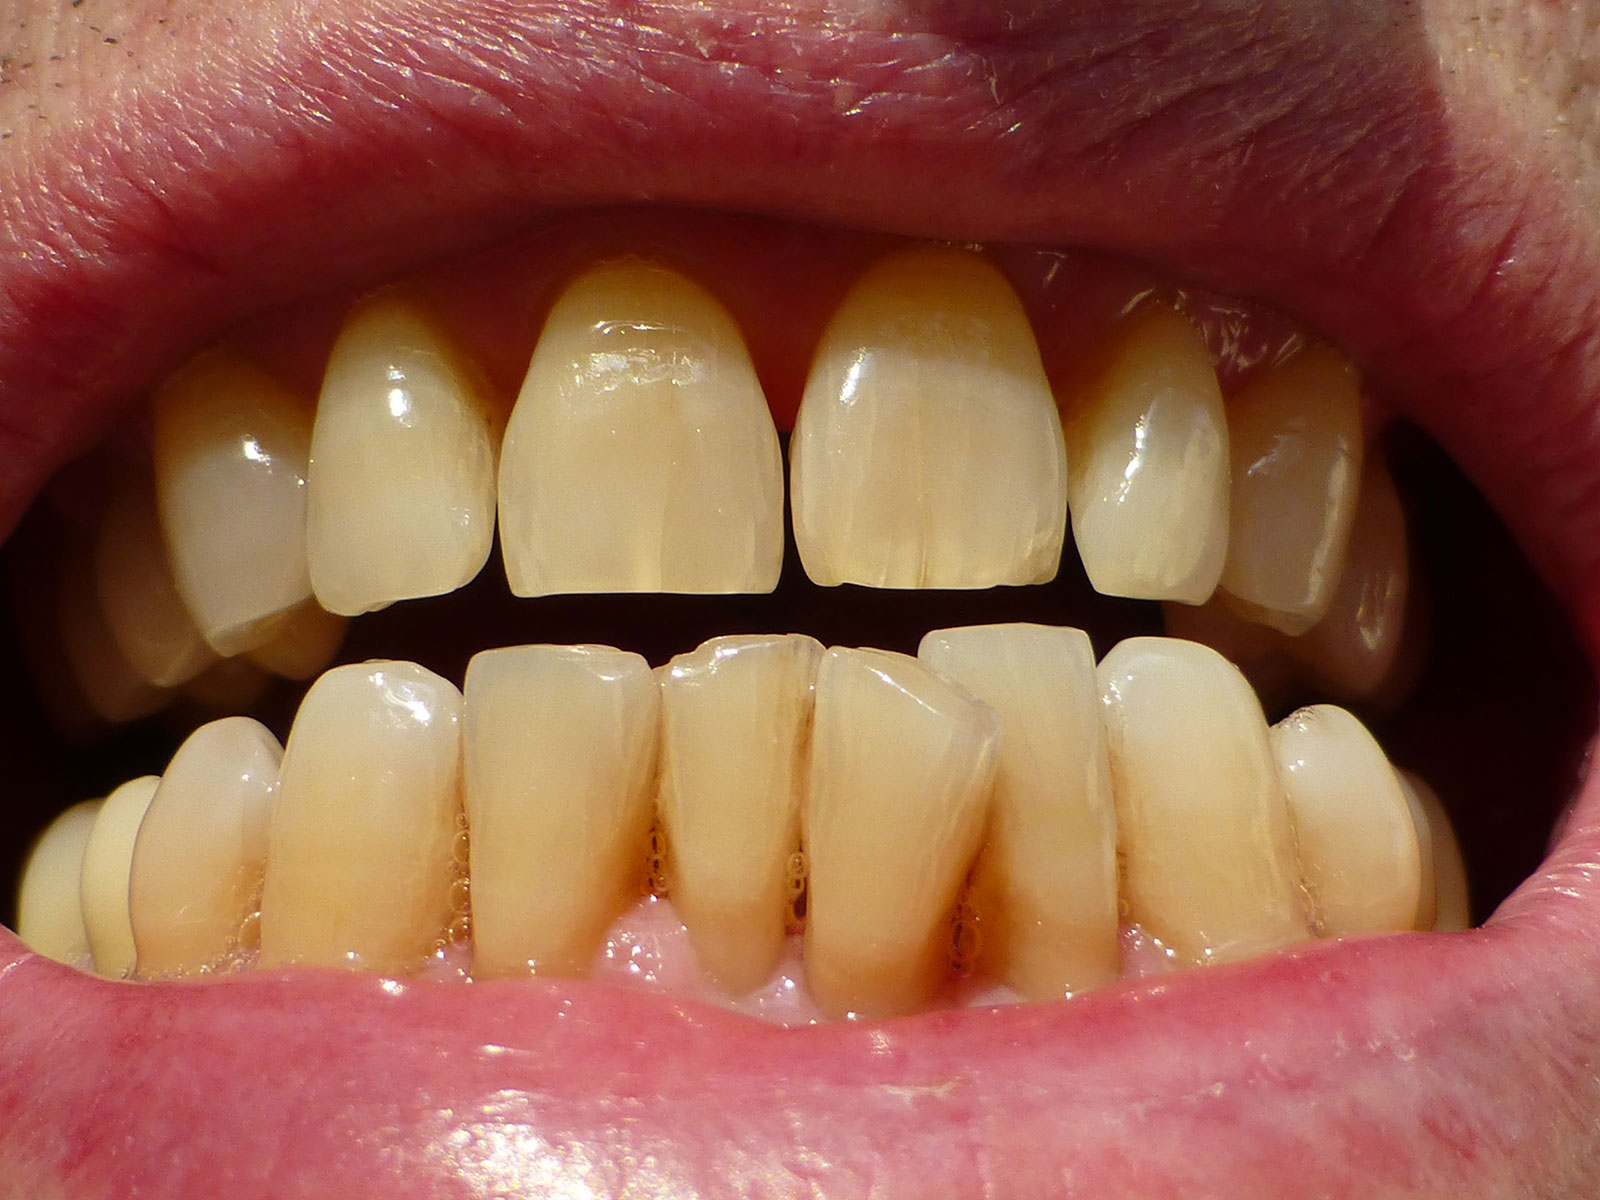

Orthognathic Surgery

Orthognathic surgery involves the surgical manipulation to correct a wide range of minor problems with the jaw and facial structure caused by growth, sleep apnea, TMJ disorders, imperfect positioning of the teeth or other orthodontic problems that cannot be fixed with braces. Surgery can help improve a person’s speaking, chewing and breathing.